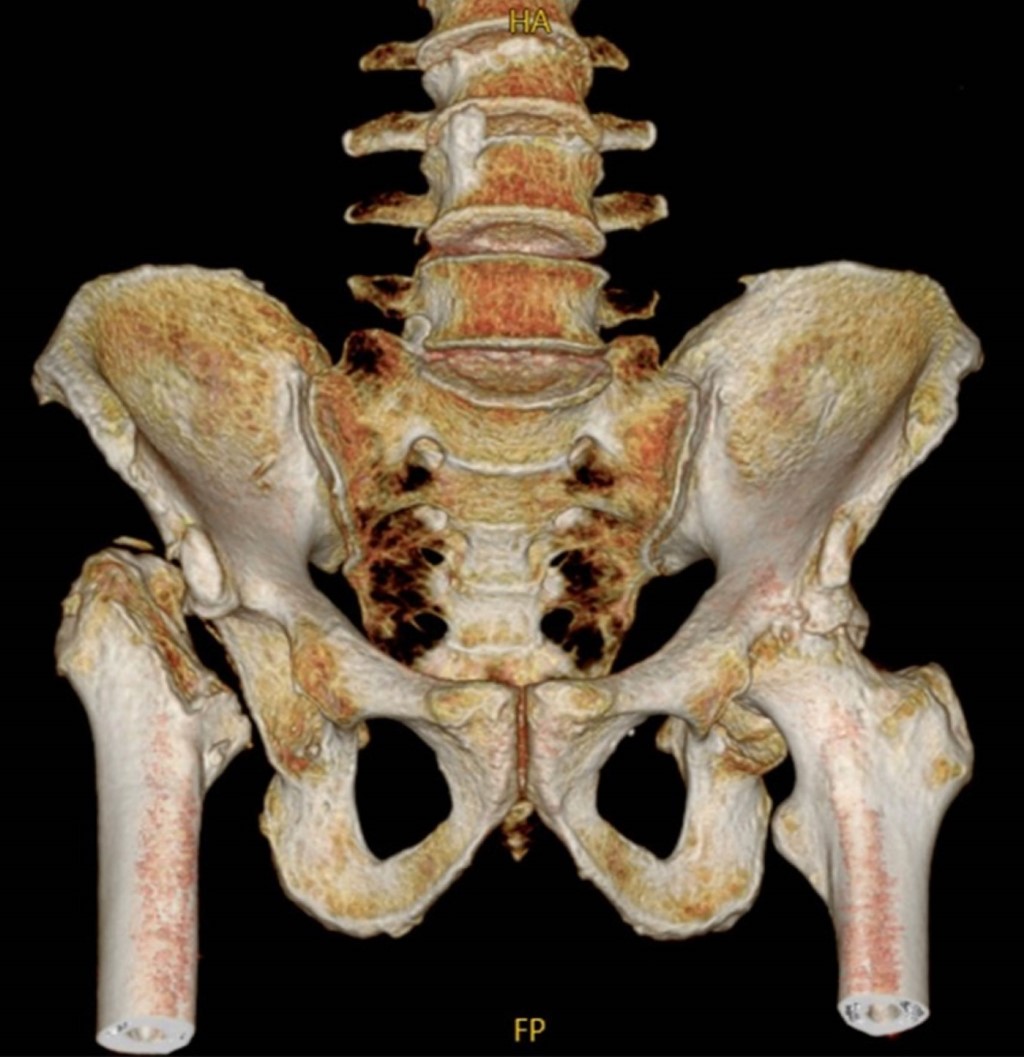

Introduction: Gorham-Stout disease is uncommon, characterized by the proliferation of endothelium-lined vessels and progressive bone destruction with spontaneous and progressive resorption. Case report: 39-year-old male with the evolution of pain in both coxofemoral joints, which increased over two years, presenting shortening of the right pelvic extremity, making ambulation impossible. The hip tomography showed disappearance of the right femoral head and neck and elevation of the greater trochanter due to dislocation, severe coxarthrosis was found in the left hip. Gorham-Stout syndrome was diagnosed and confirmed by biopsy.

Figure 2